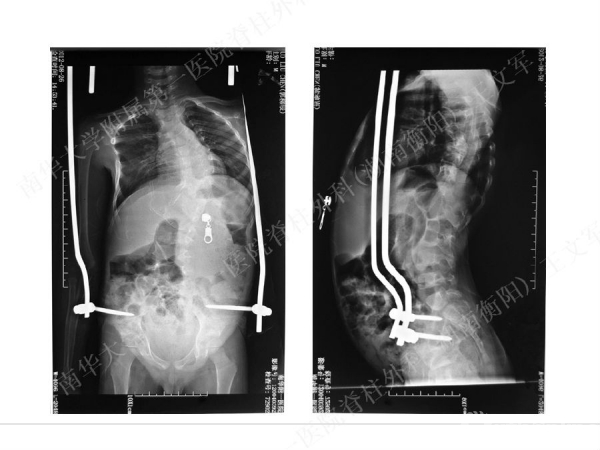

拥有完全自主知识产权的滑槽钉生长棒非融合技术,由南华大学附属第一医院脊柱外科王文军教授研发。

该技术在提供良好矫形固定效果的同时,保留了脊柱生长潜能、尽可能减少对患儿脊柱生长的影响,初步临床效果显示该系统是简单安全有效的,是严重儿童早发脊柱侧弯矫形治疗的一种有益尝试。

擅长脊柱脊髓疾病的微创及非融合手术治疗,目前率领科室开展的先进微创手术有:椎间孔镜技术、经皮穿刺腰椎外固定支架术治疗胸腰椎骨折、腹腔镜下人工腰椎间盘置换术、胸腔镜下胸椎前路手术、腰骶椎轴向融合术。率先在全国业界提出组合微创技术的理念,大大提升了脊柱微创技术的应用范围和治疗效果。拥有自主知识产权的生长棒技术在早发性脊柱侧弯术中的应用解决了儿童脊柱侧弯既早期矫形,又不影响生长发育的世界性难题。